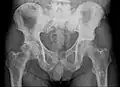

Röntgen

Für die initiale Diagnosestellung hat das konventionelle Röntgenbild eine zentrale Bedeutung. Die Indikation für Aufnahmen in zwei Ebenen ist bei dem Verdacht auf Knochentumoren immer gegeben.[85] Osteolytische Metastasen sind durch eine Abnahme der Knochendichte gekennzeichnet. Dies ist in der Röntgenaufnahme aufgrund der höheren Transparenz für Röntgenstrahlen, durch einen höheren Schwärzungsgrad zu erkennen. Umgekehrt zeigen osteoplastische Metastasen wegen der Zunahme der Knochendichte einen geringeren Schwärzungsgrad. Osteolytische Knochenmetastasen sind an der Wirbelsäule deutlich schwieriger zu erkennen; meist erst dann, wenn bereits etwa 50 % der Gesamtknochenstärke verlorengegangen ist.[85]

Röntgenaufnahme des Beckens eines Patienten mit Prostatakarzinom: Multiple osteoplastische Knochenmetastasen, insbesondere im Kreuzbein, aber auch im Darmbein, vor allem links (also rechts im Bild), am Sitzbeinhöcker links und im proximalen Oberschenkelknochen links. Nebenbefundlich zeigt sich eine Hüftgelenksarthrose rechts (also links im Bild). -